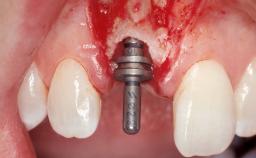

Immediate Flapless Placement of an Implant in a Maxillary Left Central Incisor Site

A 42-year-old female patient was referred to our clinic at the School of Dentistry of the University of São Paulo in November 2004, presenting a deficient restoration in the upper left central incisor. The clinical examination revealed no gingival retraction or any signs of gingival inflammation and, therefore, previous periodontal treatment was not considered. The patient presented a high lip line at full smile and a thin tissue biotype. This combination characterized a high-risk situation from an anatomic point of view, which required careful preoperative planning and cautious surgical execution.

Type of Implants One-Piece

Attachment One-Piece

Placement Protocol Immediate implant placement

Loading Protocol Immediate